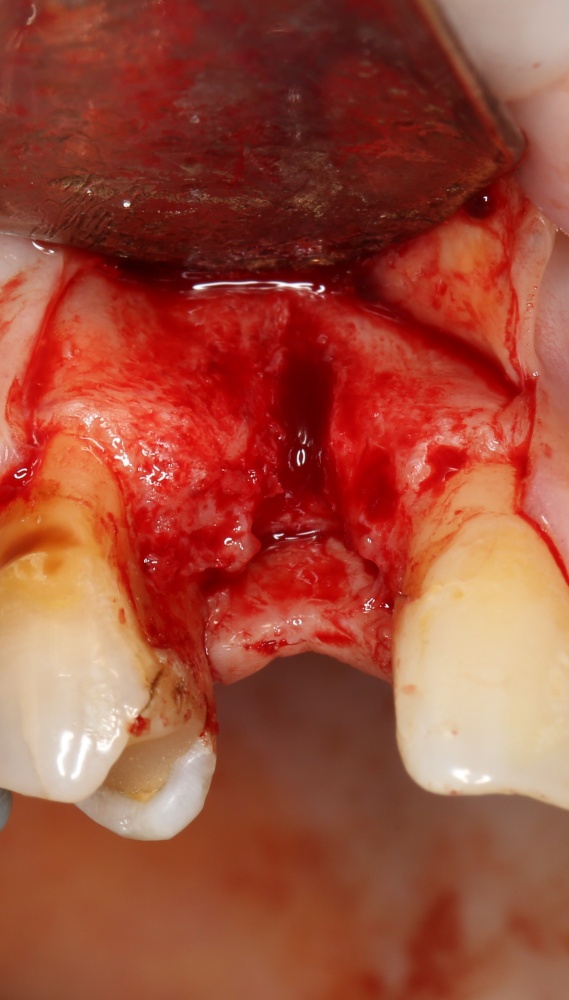

Рекомендации по установке имплантов. Для всех. Часть V.